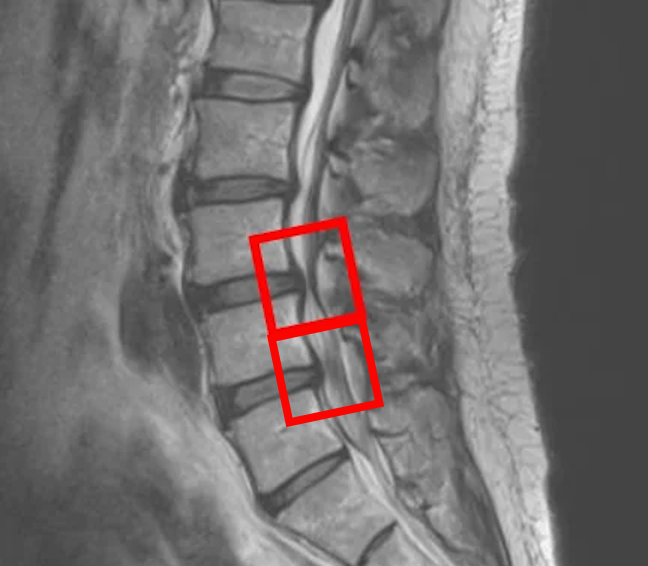

По данным МРТ выявлен переходный позвонок (L6).

По данным МРТ и результатам осмотра пациента выявлена дегенерация межпозвоночного диска L4/L5, L5/L6, а также стеноз позвоночного канала.